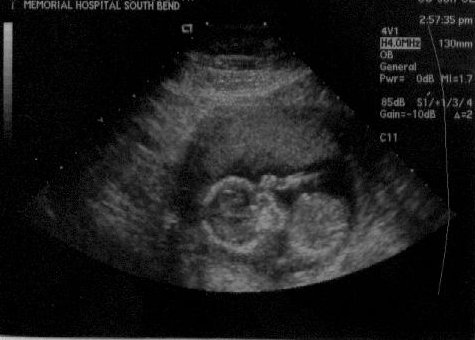

| Finally, ultrasound pictures worth looking at!! On both pictures, the head is the sphere on the left, and the body is the sphere on the right. You can also clearly see the arm and hand above the two spheres in both pictures. In fact, in the right picture, it appears that the baby might even be sucking on its thumb. The tech said everything looked great, and the baby has actually now progressed to measuing a whole week ahead! I am only 15 weeks 3 days today, but the baby is measuring 16 weeks 3 days. Click here to read more about the results of the ultrasound. (June 6, 2002 - 15 weeks, 3 days) |